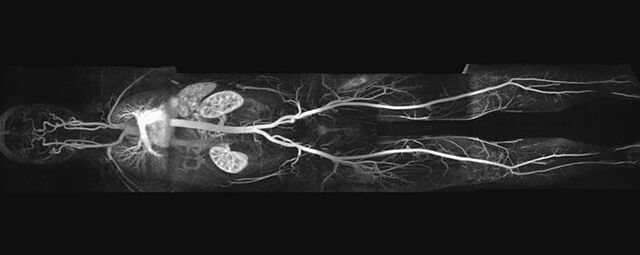

- Bauchgefäße

- Erfassung und Verlaufskontrolle bei arteriellen Aneurysmen (Aussackungen der Arterien), vor allem der Bauchaorta

- Darstellung von Gefäßengen an Nierenarterien, Baucharterien und Becken-/Beinarterien

- MR-Angiographie mit Kontrastmittel

- Erfassung arterieller und venöser Gefäße/Bypässe aller Körperregionen mit 3D-Rekonstruktion

- je nach klinischer Fragestellung zeitaufgelöste MR-Angiographie (4D-MRA) z.B. bei Frage arteriovenöse Fistel/ Shunt oder Darstellung Unterschenkelarterien vor geplanter Bypassoperation.